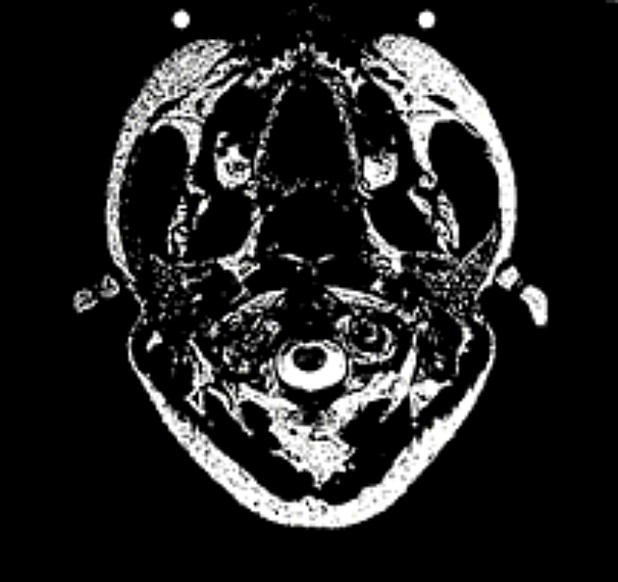

Zdjęcie stawu szyjnego wykonano podczas funkcjonalnych badań MRI w postawie pionowej. Kanał rdzenia kręgowego wykazuje obecność rdzenia kręgowego (ciemny fasolowaty kształt). Otacza go płyn mózgowy (kolor biały) (Rys.1). Charakterystyczne jest to, że już na zdjęciu wykonanym w stanie spoczynku widać zwężenie przestrzeni buforowej na skutek zgrubienia wiązadła poprzecznego (łac. Ligamentum transversum). Przestrzeń buforowa (= odległość pomiędzy szyjnym odcinkiem rdzenia kręgowego a strukturą więzadła) powinna wynosić 4–5 mm. Na zdjęciu widzimy, żejest on zwężony już w stanie spoczynku, czemu towarzyszy ściśnięcie rdzenia kręgowego (który przybrał kształt fasolki).

W normalnych warunkach jest on widoczny jako ciemna, okrągła plama. Podczas rotacji głowy w lewo (Rys.1a) duża część rdzenia kręgowego zostaje podrażniona i wgnieciona. Podczas rotacji głowy (Rys.1b) wyraźnie uwidacznia się zastój płynu mózgowo-rdzeniowego. Zastój ten rozciąga się od szyi aż po pochewkę nerwu wzrokowego.

Rys 1a / Rys 1b